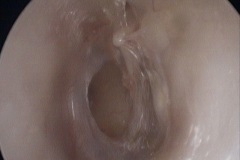

Grommet/Vent Tubes

Perforation

Tympanic Membrane